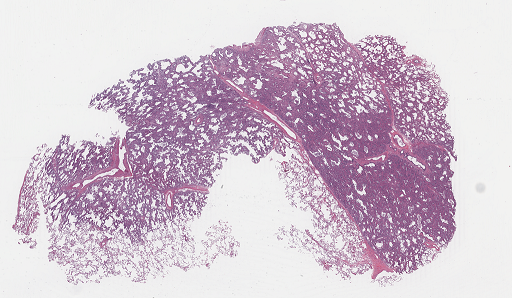

For qualitative ROI detection evaluation check Fig. 3.

Refer to caption

(a)

(b)

Figure 3: Qualitative view of ROIs recognized by Suffy through its Patch Classification. (a) An example WSI from the test set of the CAMELYON16 dataset [3]. (b) ROIs are identified by Snuffy with black lines delineating the ground truth ROIs.